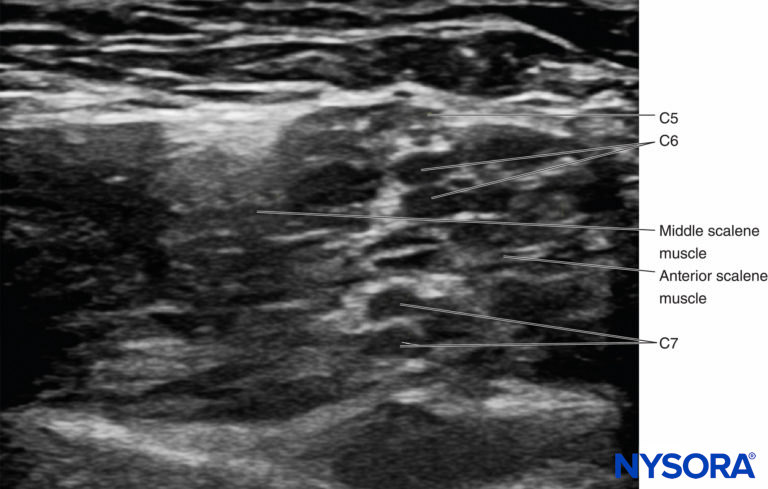

• It is common for C6 and C7 to split proximally. It is prudent to avoid injecting between the nerves coming from a single root, as this may result in an intraneural injection. Instead, it is safer to inject between C5 and C6, superficial to C5, or deep to C6 (Figure 10).

• Another relatively common anatomical variation involves the C5 root traveling through the anterior scalene for part of its course (Figure 11). To nerve block this anatomical variant, the root should be traced distally until it enters the interscalene groove.